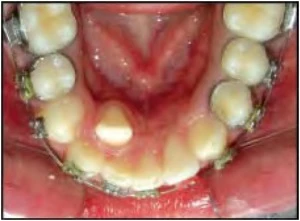

Hình 9D. Mũi tên đen chỉ vào răng nanh hàm dưới hoàn toàn nằm ngoài cung hàm và có thể bị nhổ bỏ như là một phần của kế hoạch điều trị chỉnh nha, mũi tên trắng chỉ vào một răng cối nhỏ thứ hai hàm trên bị sâu răng nghiêm trọng